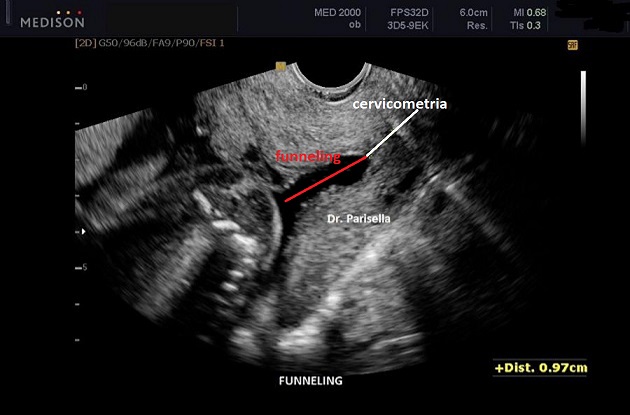

Oltre la cervicometria l'altro parametro ecografico da valutare è la morfologia e la dilatazione dell'Orifizio Uterino Interno o funneling. Se l'OUI è aperto possono essere misurate la lunghezza (immagini 5-6) e la larghezza della svasatura anche se la larghezza  ha meno importanza.

Da vari studi emerge che il funneling rappresenta una caratteristica di ingravescenza, insieme al collo raccorciato, nella progressione verso il parto pretermine. Nel 70% dei casi di collo raccorciato è presente anche il funneling. Se il collo non è raccorciato la presenza di funneling non incrementa il rischio di parto pretermine.

Il funneling deve essere valutato in termini percentuali (PF - Percentuale di Funneling): lunghezza del funneling diviso per la CL Totale (immagini 6 - 7); la CL Totale è la somma della lunghezza del funneling e della CL Funzionale (immagini 6 - 7); la CL funzionale è la lunghezza della porzione chiusa del canale cervicale, cioè la porzione di canale cervicale che normalmente viene misurata in ecografia e per questo denominata anche CL Ecografica (immagine 6 ).

Il rilievo di una CL inferiore a 25 mm., alla stessa stregua di una PF superiore al 25%, è predittiva di RPP e quasi sempre una PF superiore al 25% è associata a CL < 25 mm.

Le due condizioni associate, PF > 25% e CL < 25 mm., indicano un aumento di rischio di parto pretermine con una sensibilità del 74%, mentre la presenza di funneling con CL normale non sembra aumentare il rischio di parto pretermine.